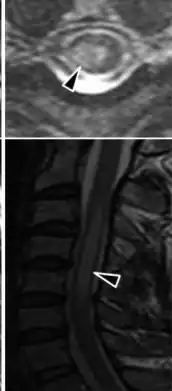

Myelitis has an extensive differential diagnosis. The type of onset (acute versus subacute/chronic) along with associated symptoms such as the presence of pain, constitutional symptoms that encompass fever, malaise, weight loss or a cutaneous rash may help identify the cause of myelitis. In order to establish a diagnosis of myelitis, one has to localize the spinal cord level, and exclude cerebral and neuromuscular diseases. Also a detailed medical history, a careful neurologic examination, and imaging studies using magnetic resonance imaging (MRI) are needed. In respect to the cause of the process, further work-up would help identify the cause and guide treatment. Full spine MRI is warranted, especially with acute onset myelitis, to evaluate for structural lesions that may require surgical intervention, or disseminated disease.[11] Adding gadolinium further increases diagnostic sensitivity. A brain MRI may be needed to identify the extent of central nervous system (CNS) involvement. Lumbar puncture is important for the diagnosis of acute myelitis when a tumoral process, inflammatory or infectious cause are suspected, or the MRI is normal or non-specific. Complementary blood tests are also of value in establishing a firm diagnosis. Rarely, a biopsy of a mass lesion may become necessary when the cause is uncertain. However, in 15–30% of people with subacute or chronic myelitis, a clear cause is never uncovered.[9]